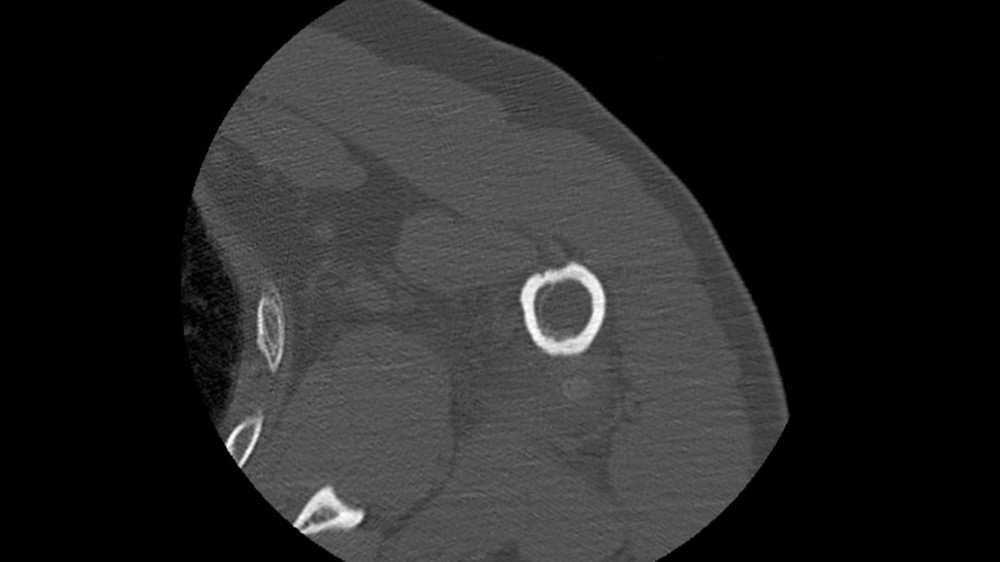

Gortais / Biyoukar / Miquel / Parlier-Cau 19/01/2022